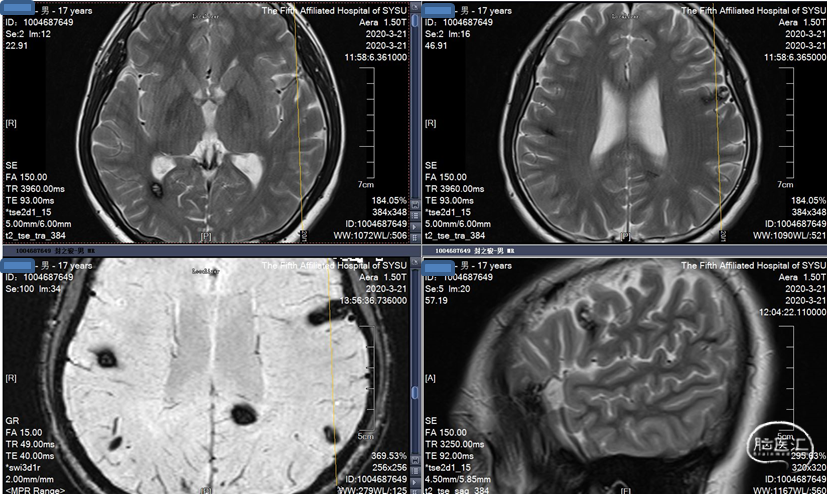

MRI 扫描:有边界,呈圆形。病灶在 T1 加权像呈等信号,在 T2 加权像或注射对比剂后呈高信号,病灶内有混杂低信号,病灶周围有环形低信号带。小型 (<1 cm) 以及非出血性海绵状血管瘤,磁敏感加权成像(SWI)的检出率更高。